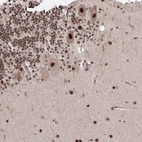

Immunohistochemical staining of human cerebellum shows strong nuclear positivity in Purkinje cells.